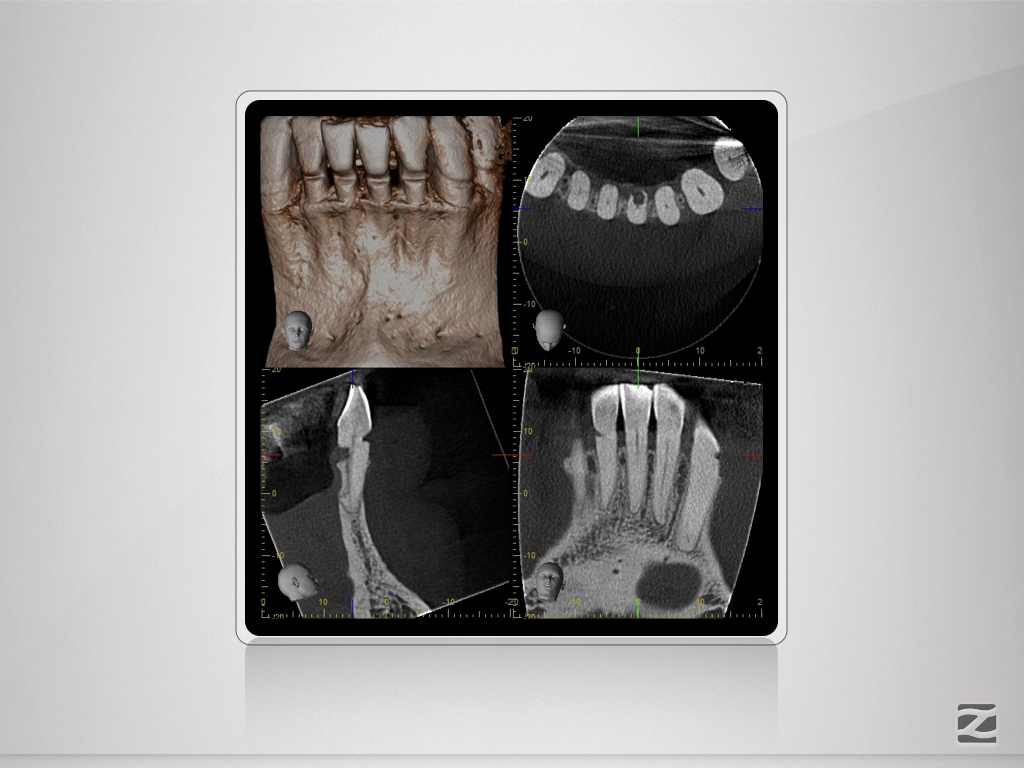

31D.012

Trauma, externe Resorption & Pulpotomie